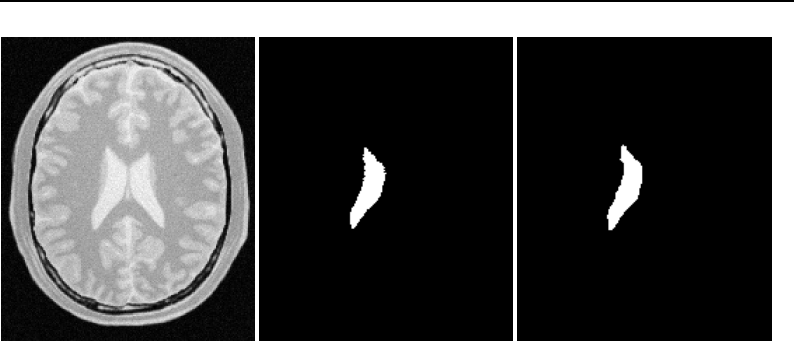

The National Library of Medicine Insight Segmentation and Registration Toolkit, shortened as the

Insight Toolkit (ITK), is an open-source software toolkit for performing registration and segmenta-

tion. Segmentation is the process of identifying and classifying data found in a digitally sampled

representation. Typically the sampled representation is an image acquired from such medical instru-

mentation as CT or MRI scanners. Registration is the task of aligning or developing correspondences

between data. For example, in the medical environment, a CT scan may be aligned with a MRI scan

in order to combine the information contained in both.